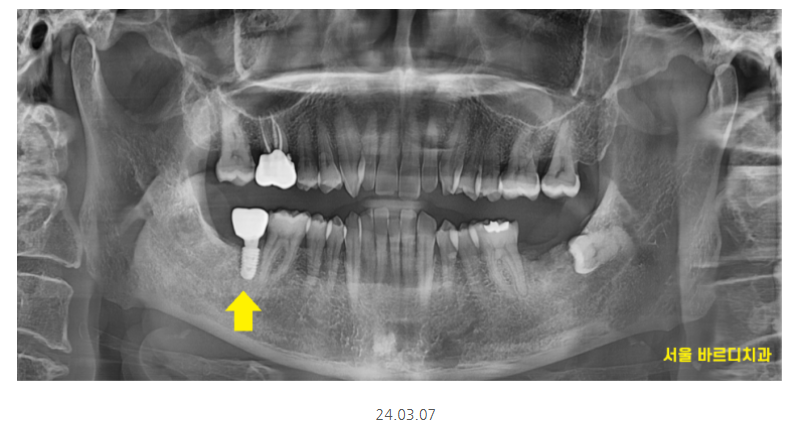

하남시청치과 임플란트 그 결과는,,?

짜잔~~

원하는 위치에 정확히 들어갔습니다.

3개월 뒤에 뼈와 충분히 붙어서

기둥을 올리고 보철을 올려드렸습니다.